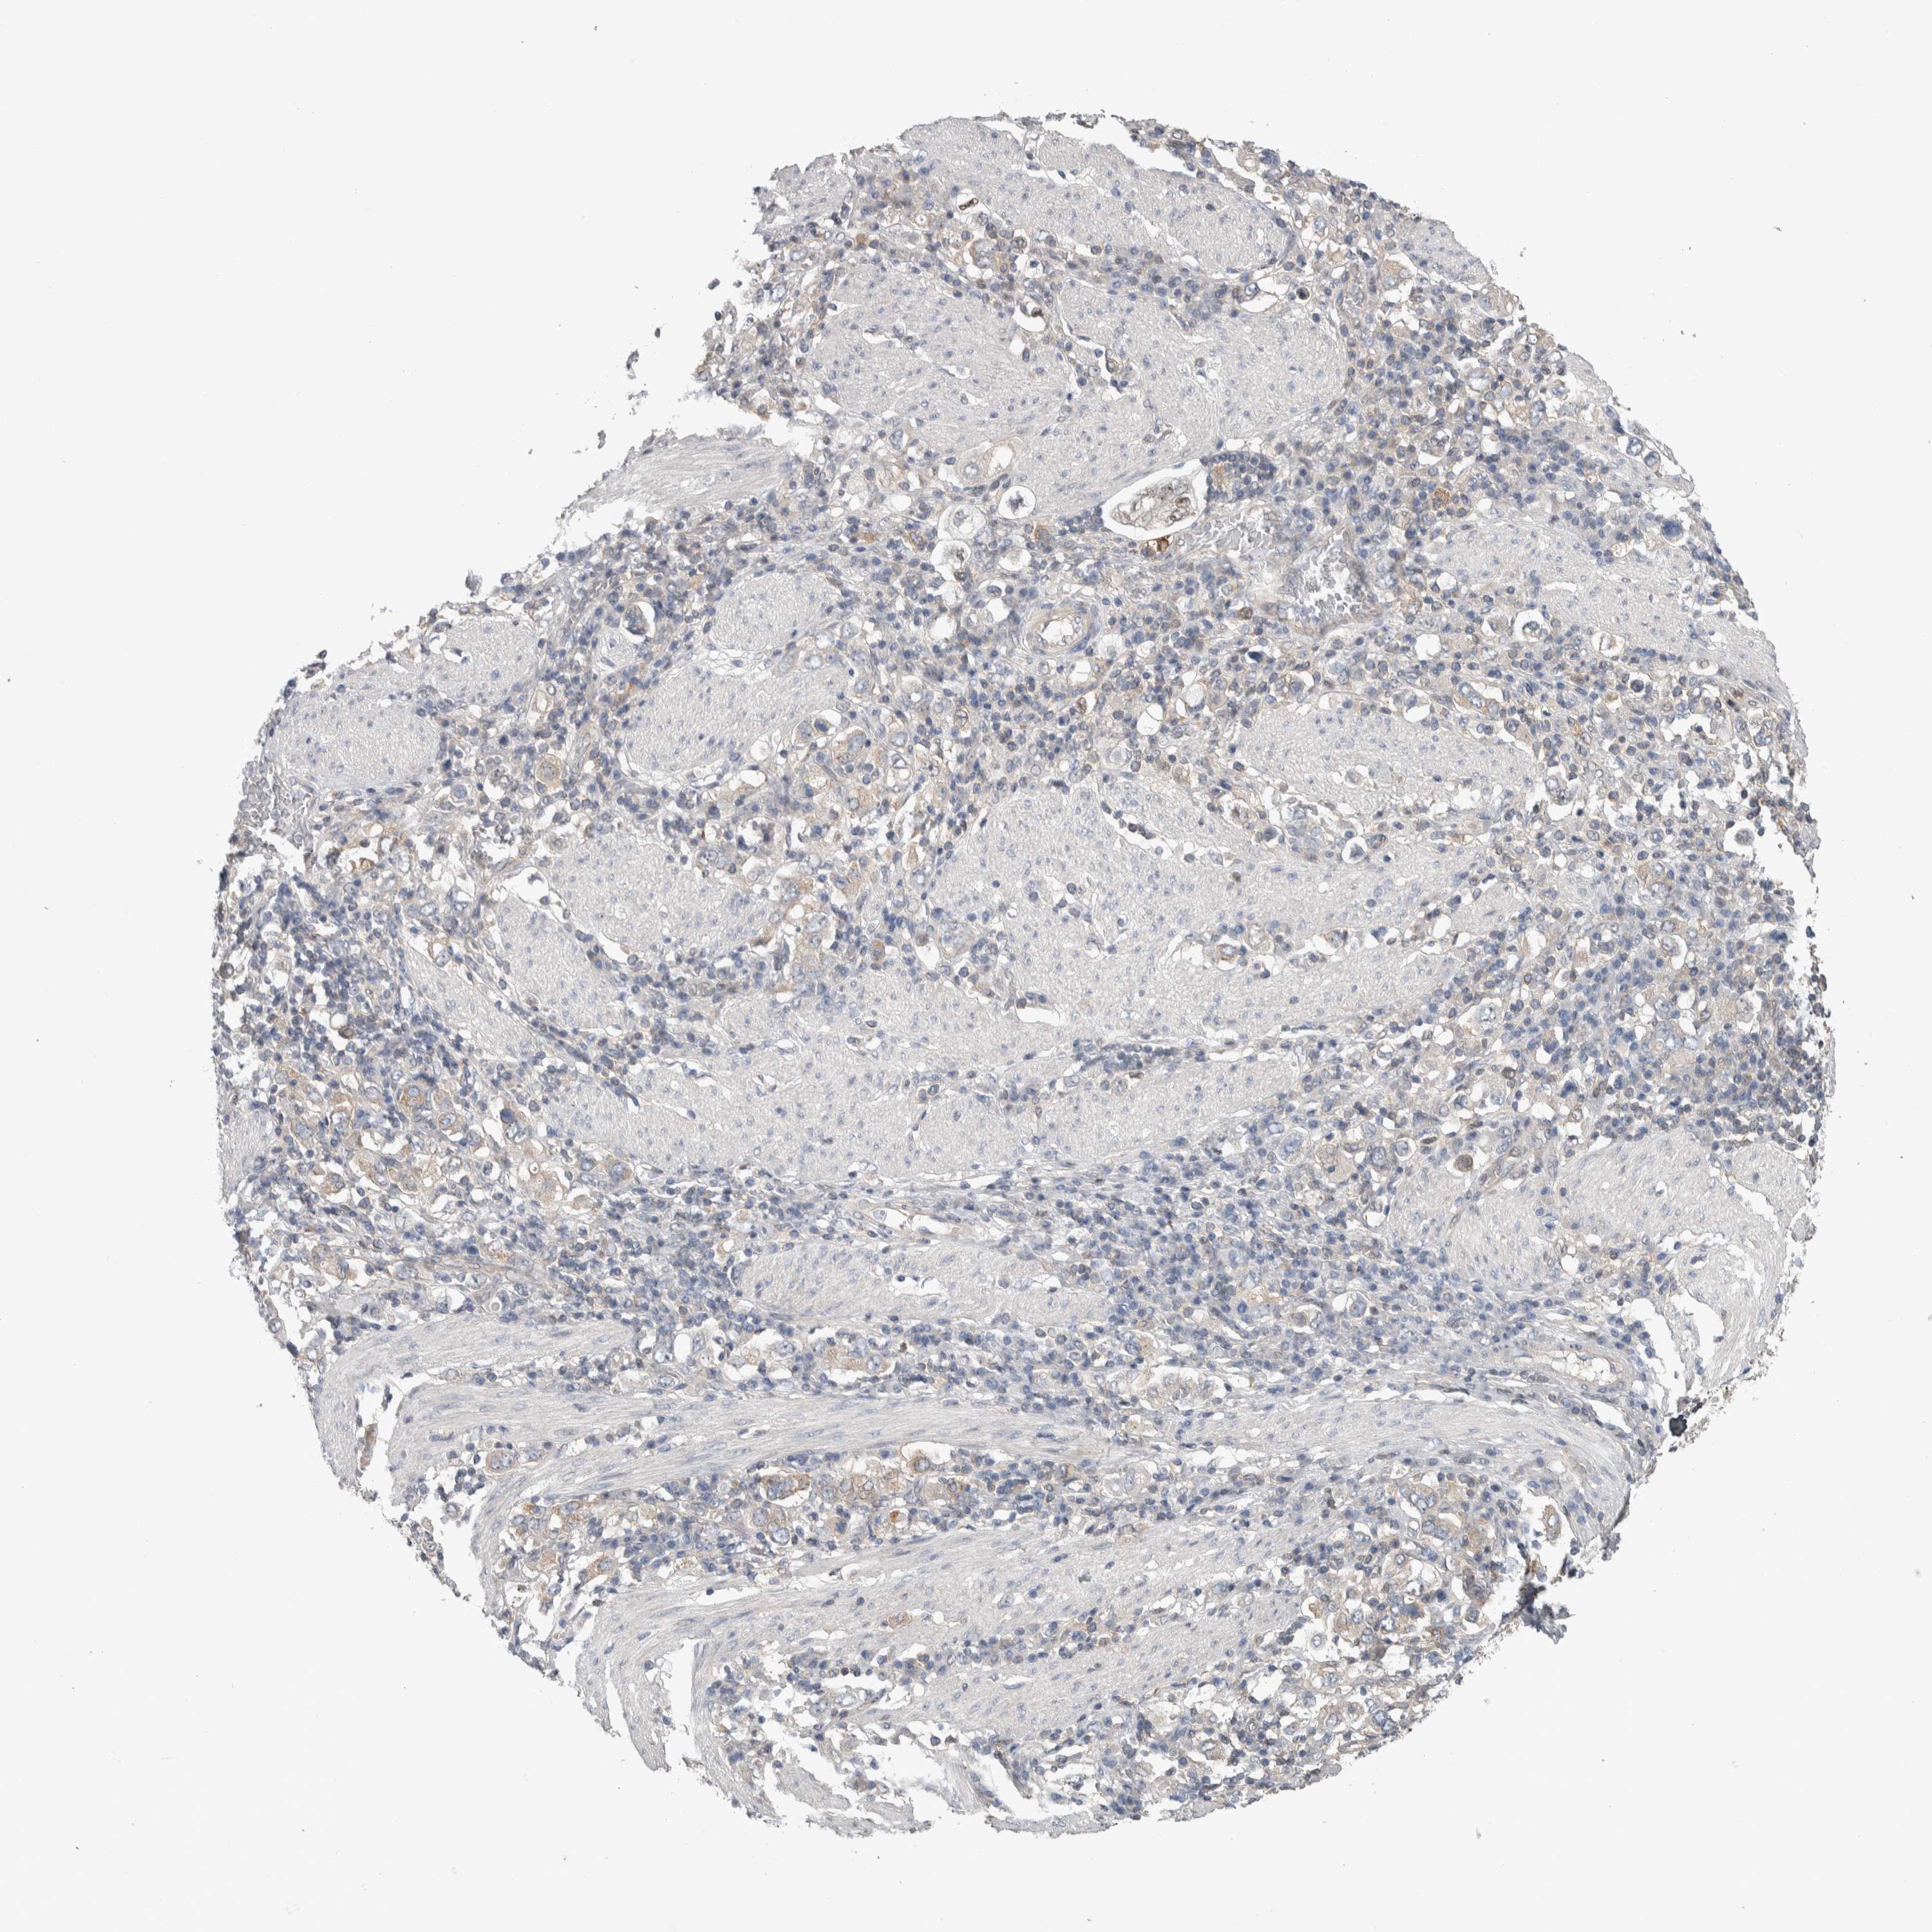

STOMACH CANCER - Protein expressioni

A mouse-over function shows sample information and annotation data. Click on an image to view it in a full screen mode. Samples can be filtered based on level of antibody staining by selecting one or several of the following categories: high, medium, low and not detected. The assay and annotation is described here.

Antibody stainingi

Antibody staining in the annotated cell types in the current human tissue is reported as not detected, low, medium, or high, based on conventional immunohistochemistry profiling in selected tissues. This score is based on the combination of the staining intensity and fraction of stained cells.

Each image is clickable and will lead to virtual microscopy that enables deeper exploration of all samples and also displays staining intensity scores, fraction scores and subcellular localization as well as patient and tissue information for each sample.

Antibody HPA024432

Staining

High

Medium

Low

Not detected

Intensity

Strong

Moderate

Weak

Negative

Quantity

>75%

75%-25%

<25%

None

Location

Nuclear

Cytoplasmic/membranous

Cytoplasmic/membranous,nuclear

Adenocarcinoma, NOS